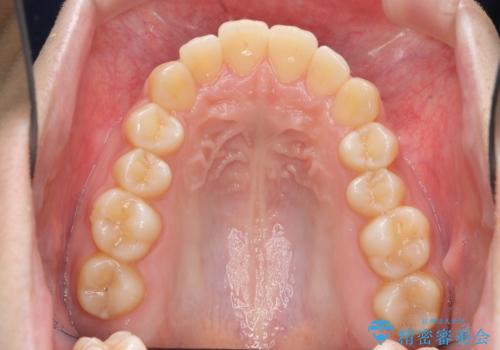

上の歯を全体に大きく後ろに下げる治療計画を立てました。

後ろに下げるために、親知らずは抜歯しています。

後ろに下げるために、ワイヤー矯正の前にカリエールという装置を使用しました。